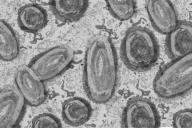

Он отметил, что в общей сложности оспой обезьян заболели более 18 тысяч человек в 78 государствах.

По информации руководителя  Европейского бюро ВОЗ Ханса Клюге, на территории Европы с мая зафиксировано порядка 12 тысяч подтвержденных или предполагаемых случаев инфицирования вирусом оспы обезьян.

Всемирная организация здравоохранения информирует о том, что на сегодняшний день выявлено около 14 тысяч заражения оспой обезьян.

В общей сложности зарегистрировано 9200 случаев инфицирования данным вирусом.

На данный момент более чем в 50 государствах зафиксировано больше пяти тысяч случае инфицирования вирусом оспы обезьян.

На заседании членов комитета большинством голосов было принято решение об информировании гендиректора Всемирной организации здравоохранения о необходимости отнесения вируса оспы обезьян к чрезвычайной ситуации международного значения.

За последние месяцы в мире фиксируется все больше случаев оспы обезьян.

Европа на данный момент остается эпицентром вспышки обезьяньей оспы, в регионе уже обнаружено больше 1,5 тысячи случаев заражения, это составляет 85% от всего числа заболевших.

Всемирная организация здравоохранения сообщает о более чем полутора тысячи подтвержденных случаев обезьяньей оспы.

Всего сообщается о 643 случаях инфицирования оспой обезьян за период с 13 мая по 1 июня.